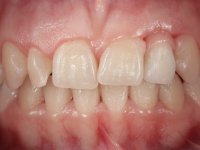

Female patient, 24 years of age, non-smoker. The clinical situation resulted from an orthodontic treatment performed with the intention of resolving a problem of unilateral agenesis of the left lateral incisor. After orthodontic correction, an implant was placed at the site of tooth 2.2. During the period of osseointegration the patient used a removable orthodontic appliance with a prosthetic tooth. Upon assessment of the situation, I registered the following aesthetic conditions:

1. The cervical level of the teeth 1.3.1.2 and 1.1 are at a more incisal level than the teeth 2.1 and 2.3.

2. The distal papillae of 2.1 and mesial of 2.3 disappeared.

3. Slight radicular exposure in distal 2.1 and mesial 2.3.

4. The edentulous space corresponding to the high and narrow 2.2.

5. Tooth 1.2 with microdontia and rolled.

An impression was made on the implant with open tray technique using soft and regular consistency putty. At the laboratory, after confection of the work model, a diagnostic waxing was performed, which sought to find an aesthetic compromise solution. In this sense, a temporary workpiece screwed onto the implant was used to simulate the difficulties we would have with screwing the definitive work. This study abutment consisted of wax to reproduce soft and hard tissues, seeking to anticipate the use of ceramics of gingival and coronary shade. Also, part of the interproximal papillae corresponding to the distal portion of the 2.1 tooth and the mesial tooth of the tooth 2.3 were also waxed, anticipating the use of composite resin “chips” with gingival tonality. Finally, a veneer was waxed to correct the microdontia of the tooth 1.2. In this waxing, the vestibular emergence of the orifice for access to the screw of the implant abutment was evident. Once this therapeutic option was accepted, the implant abutment in polymerized composite resin was prepared at the lab, as well as the papillary "chips", also in composite resin of gingival tonality. Tested in the mouth, the abutment was screwed and the "chips" bonded. The access hole of the screw was filled with composite resin. In subsequent consultation, a gingivectomy was performed on the cervical contour of teeth 1.3, 1.2 and 1.1 with the aim of correcting the asymmetry between the first and second quadrant. After the soft tissues were cicatrized, a dental bleaching was performed according to the patient’s aesthetic requirements. Final impression on the implant was made using the silicone open tray technique, taking care to individualize the transfer piece by copying the emergence profile of the patient’s provisional abutment. At the laboratory, the impression yielded a definitive working model, on which the abutment was waxed on a plastic insert. This process was carried out with the orientation of a wall of silicone based on diagnostic waxing. The wax made on the plastic part was placed in a special holder that allowed its scanning in a laboratory scanner. This scan by CAD process informed the design of an abutment in Zr. later materialized by a CAM process. The Zr. abutment was tested in the mouth, validating its clinical and imaging establishment. During this consultation, the choice of color was made by the ceramist, of both the coronary ceramics and the ceramic of gingival tonality to be used. Individualized color scales were used. At the laboratory, the coronary and gingival ceramics were placed on the implant abutment and later, on a working model with refractory gypsum, a veneer of feldspathic ceramic was made. This veneer was built on a surface specially designed for this purpose in the abutment. This surface tried to reproduce a dental preparation performed for the same effect. In the mouth the abutment was screwed with a torque of 35N, the access hole to the screw was filled with Teflon and later filled with composite resin. The veneer was bonded onto the implant abutment using the conventional bonding technique, with relative insulation. For economic reasons, the patient did not proceed to perform the veneer on tooth 1.2. Although a limited aesthetic compromise was expected from the outset, a result was achieved which satisfied the patient.